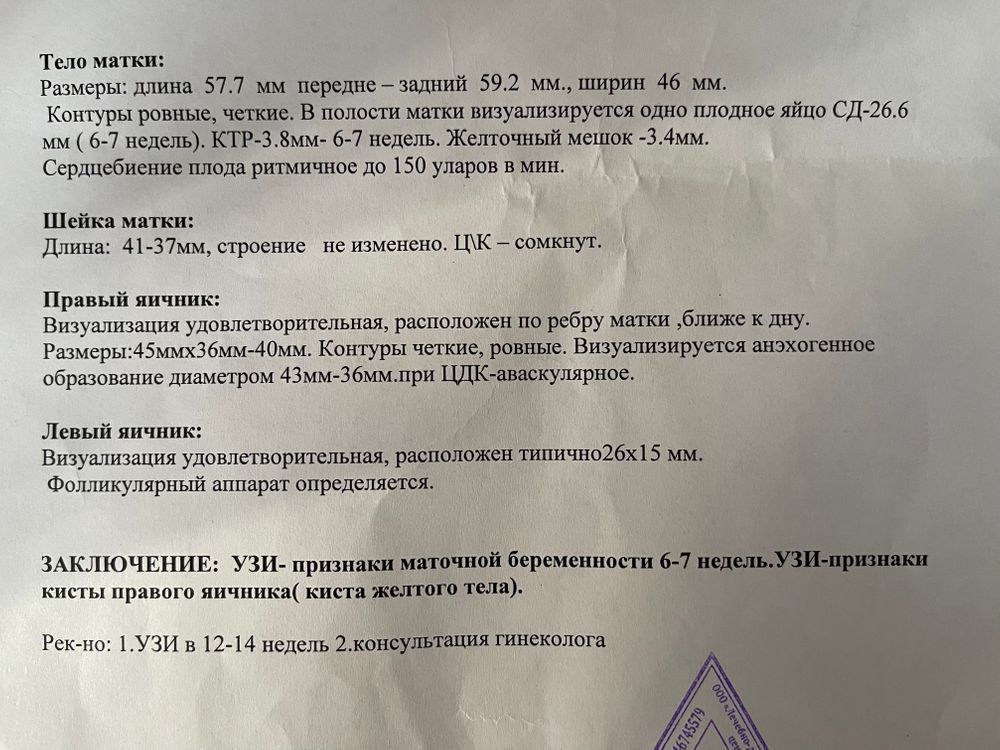

Моя бусинка появилась 😍сердечко бьется. Прикрепилась высоко. Размеры на 6-7 недель. Сказали все хорошо. Но есть киста на правом яичнике довольна большая. Правый яичник у меня частично удалён после лапароскопии. Он уже недели 1,5 переодически колет. Судя по размерам киста даже больше левого яичника.

Узи в 7 недель.